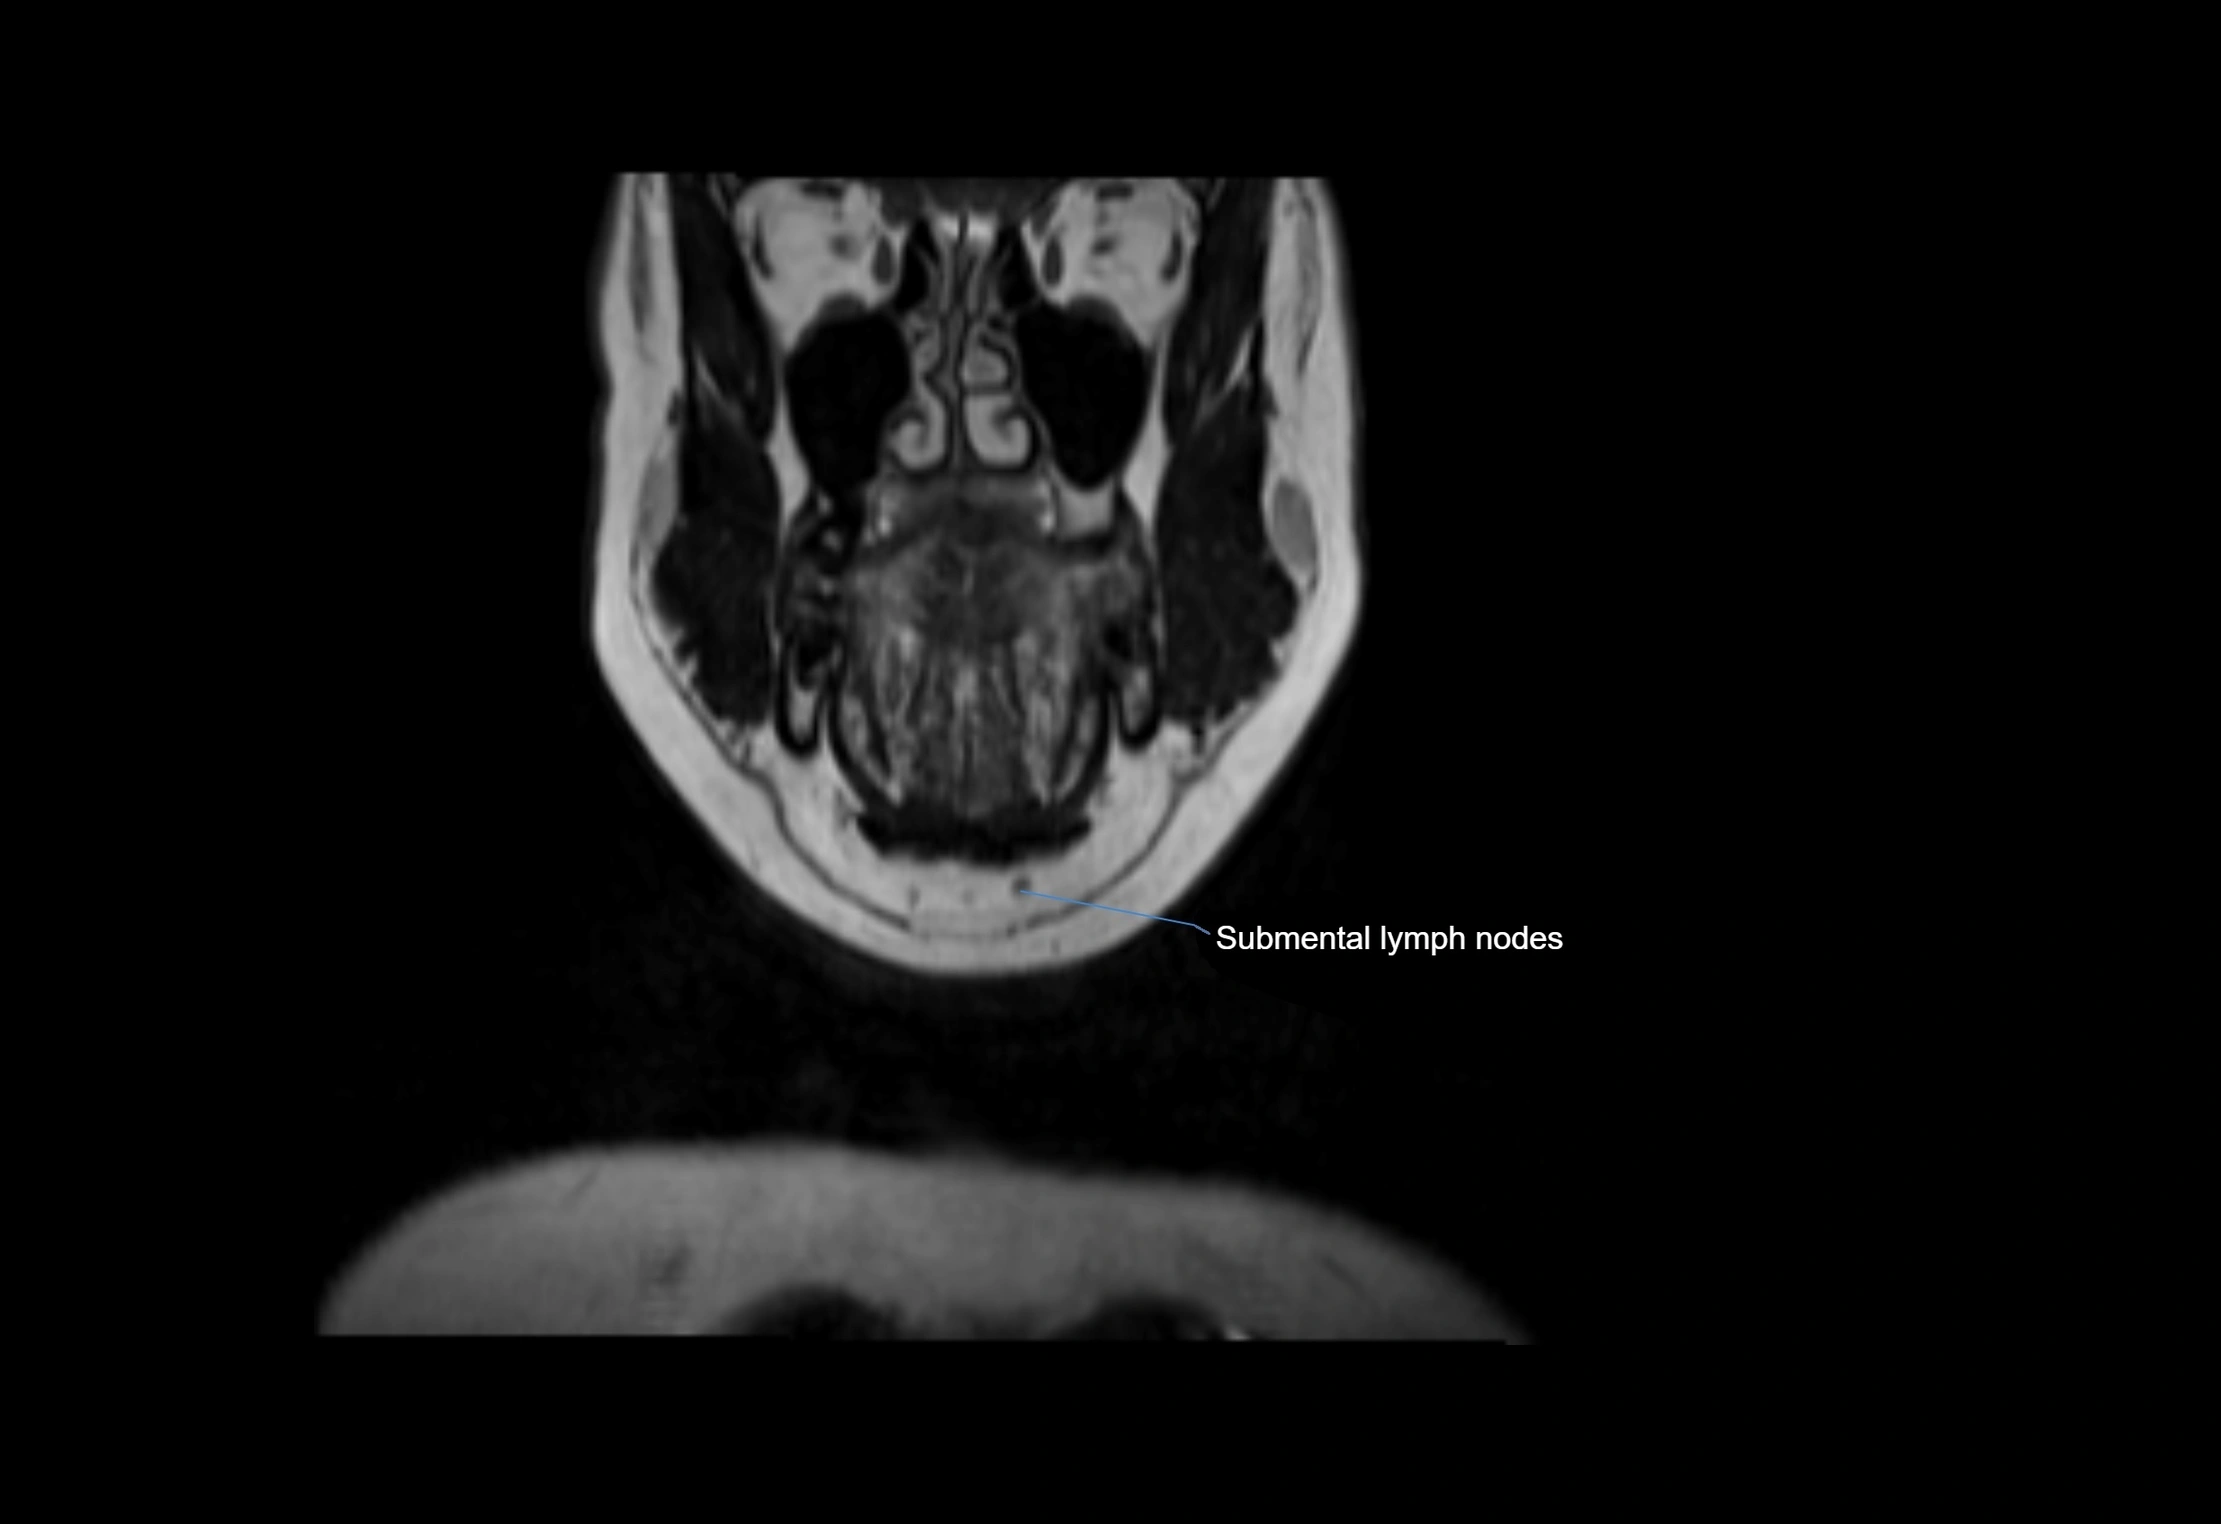

MRI Appearance

T1-weighted images:

• Normal accessory nodes appear as small, oval hypointense to intermediate signal structures within subcutaneous fat

• Surrounded by hyperintense fat, enhancing contrast for visualization

T2-weighted images:

• Nodes show intermediate signal, with surrounding fat bright

• Useful for detecting edema, inflammation, or infiltration

• Fatty hilum may appear slightly hyperintense relative to cortex

MRI images

image